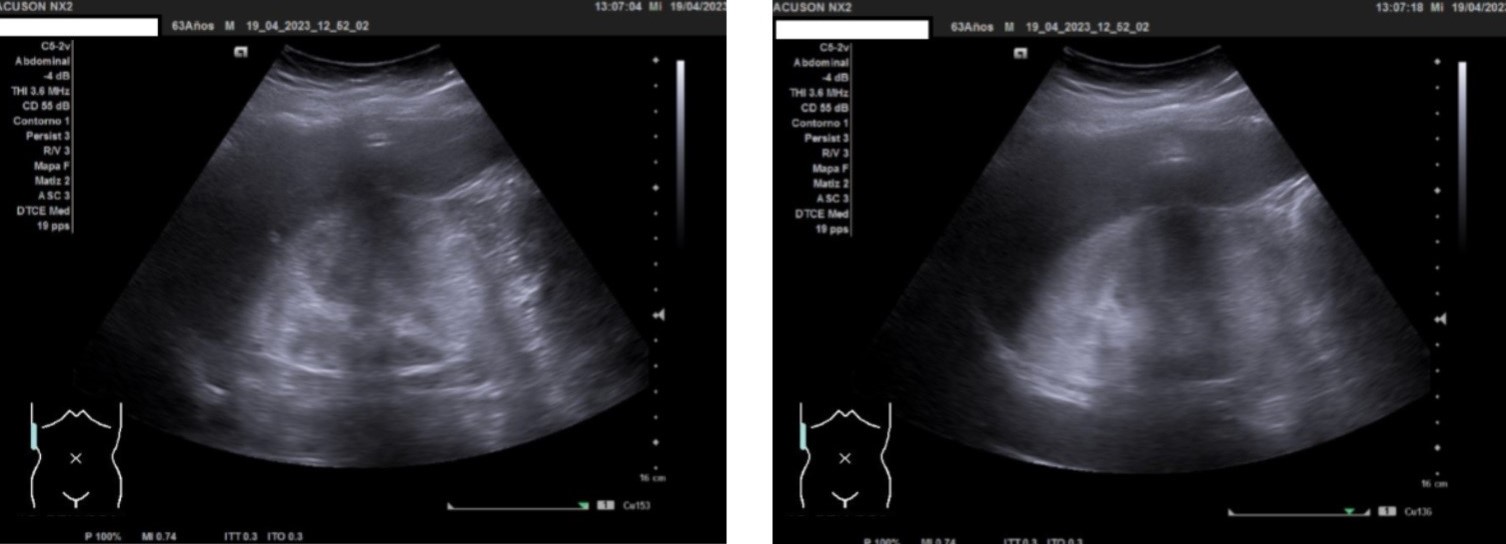

Hallazgos ecográficos

Ecografía clínica urológica: se observa imagen hiperecogénica a nivel de polo superior de riñón derecho que no capta al Doppler color y que mide 10 cm.